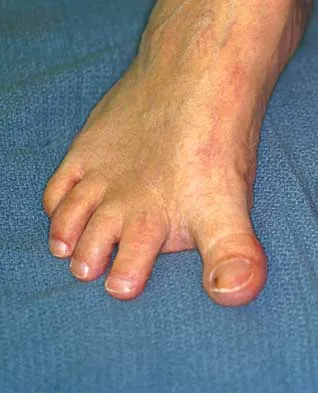

The condition shown in Figures 9a and 9b is most likely the result of

Explanation

The clinical photograph and radiograph show gout, which is the result of urate deposition in the joint and soft tissues. Radiographs frequently reveal periarticular erosions. The crystals are intracellular and negatively birefringent under the polarized microscope. Treatment for acute flares include colchicines, indomethacin, and corticosteroids (including injections). Medications such as allopurinol help prevent recurrent flares. Tophi such as that seen in this patient are often confused with and associated with infection. Wortmann RL, Kelley WM: Crystal-induced inflammation: Gout and hyperuricemia, in Harris ED, Budd RC, Firestein GS, et al (eds): Kelley's Textbook of Rheumatology, ed 7. New York, NY, Elsevier Science, 2005, pp 1402-1429. Trumble TE (ed): Hand Surgery Update 3: Hand, Elbow, & Shoulder. Rosemont, IL, American Society for Surgery of the Hand, 2003, pp 433-457.